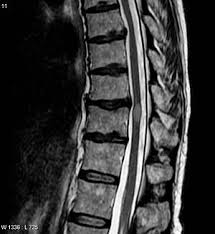

Transverse Myelitis Symptoms - Eposters Intravascular Lymphoma Presenting As Transverse Myelitis In A Patient With Myelodysplastic Syndrome _ Transverse myelitis affects men and women of all ages and races.. Transverse myelitis usually affects both sides of the body below the affected area of the spinal cord, but sometimes there are symptoms on just one side of the body. Or, they may develop over 1 to 4 weeks. Transverse myelitis (tm) is a rare neurological condition in which the spinal cord is inflamed. Tm causes motor weakness, a sensory impairment below the lesions, and bowel and bladder dysfunction. The onset of transverse myelitis is acute to subacute.

Tm causes motor weakness, a sensory impairment below the lesions, and bowel and bladder dysfunction. Increased urinary urgency, bowel or bladder incontinence, difficulty or inability to void, and incomplete evacuation of bowel or constipation are other characteristic autonomic symptoms. Transverse implies that the inflammation extends horizontally across the spinal cord. Patients may have only one symptom, or a combination of the following: Symptoms can quickly become severe.

Impairments may include severe weakness, muscle stiffness and spasms, paralysis, incontinence, or chronic neuropathic pain. It can also signal a relapse. Weakness of the legs and/or arms: The segment (location) of the spinal cord where the damage occurs determines which parts of the body are affected; Vertically, the lesion spans no more than three vertebrae. Typical signs and symptoms include: Symptoms of transverse myelitis may develop within a few hours or days. Many people with transverse myelitis will recover with minor or no permanent problems.

Chronic pain is a common complication of transverse myelitis. The symptoms of transverse myelitis can develop over several hours or days, or over a longer period of 1 to 2 weeks. Transverse myelitis (tm) is a rare neurological condition in which the spinal cord is inflamed. Symptoms transverse myelitis appears differently in individuals depending on the severity of the demyelination. Transverse myelitis affects men and women of all ages and races. The segment of the spinal cord that has inflammation or damage determines the symptoms a person has. Tm causes motor weakness, a sensory impairment below the lesions, and bowel and bladder dysfunction. Back or neck pain weakness in arms or legs Impairments may include severe weakness, muscle stiffness and spasms, paralysis, incontinence, or chronic neuropathic pain. Partial transverse myelitis and partial myelitis are terms sometimes used to specify inflammation that only affects part of the width of the spinal cord. Abrupt changes in vision caused by optic neuritis include: Vertically, the lesion spans no more than three vertebrae. Typical signs and symptoms include:

Extreme sensitivity to touch is also present in about 80 percent of people with. Transverse myelitis (tm) is a rare neurological condition in which the spinal cord is inflamed. The onset of transverse myelitis is acute to subacute. Abrupt changes in vision caused by optic neuritis include: Typical signs and symptoms include: In this type, inflammation covers the full width of the spinal cord section. Many people with transverse myelitis will recover with minor or no permanent problems. Weakness in the legs and arms: Transverse implies that the inflammation extends horizontally across the spinal cord. Generally, inflammation at one segment causes symptoms at that level and below that level. People with symptoms of transverse myelitis may: Transverse myelitis is a neurological disorder caused by inflammation of the spinal cord, which carries nerve signals from the brain to the rest of the body. Pain, which may begin suddenly in the lower back.